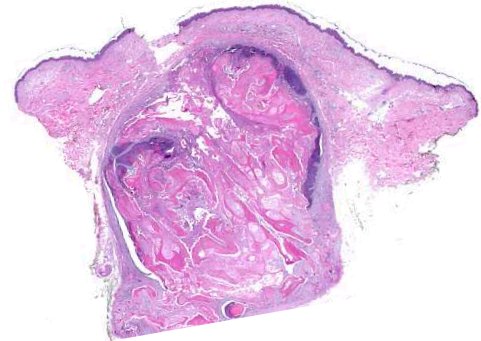

This young female complains of whitish lesions affecting her eyelids especially of the lower lids. The histology is as shown.

Syringoma

Syringoma showing ducts surrounded by the abnormal epithelial cells.